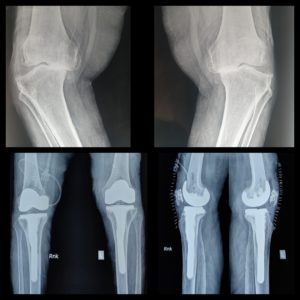

History: 70-yr-old lady was unable to walk because of severe deformities.

Case: This lady was operated by Dr. Amyn Rajani few days back. A long stem in the tibia is very important in such cases to prevent periprosthetic fracture. Due to sudden change of alignment there is too much load on tibia and hence the long stem